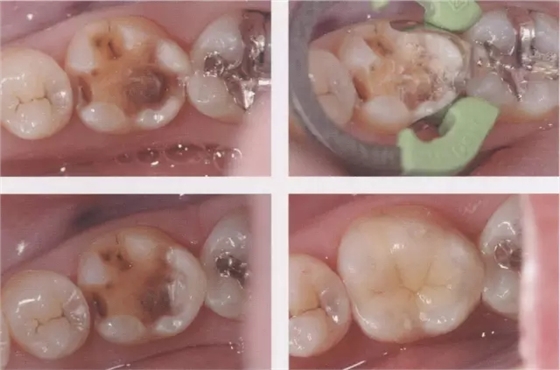

1、嵌體和高嵌體 在磨牙區(qū)域,由于牙齒近中面以及遠中面的傾斜程度不同,常會遇到分離困難的病例。例如,智齒的近中根傾斜,引起鄰牙根間隙過窄的情況。相鄰牙齒的近中傾斜,牙冠進入被處理牙倒凹處的情況(圖2、3)。以上情況,鄰接面由于齲齒形成窩洞,即便是運氣好在齦下做了分離,也會因為出血造成取模困難、頰舌的成形變大。所以采取以下處理措施。 1、術(shù)前拍攝牙片,根據(jù)牙根的傾斜判斷有沒有引起鄰牙根間隙過窄的情況。若沒有傾斜,就是簡單病例。 2、若智齒沒有對合牙,也考慮拔除智齒。 3、鄰接面用樹脂填充之后,用間接法進行烤瓷嵌體或烤瓷高嵌體修復(fù)。 1、貼面治療 對于變色牙齒進行貼面治療的情況下,牙頸部觀察無變色的情況下,可直接在齦上做成形。普通成形深度能夠保存牙釉質(zhì),因而判斷為簡單病例。(圖4) 如果牙頸出現(xiàn)變色,就需要進行齦下成形,難度增加。如果也存在前突問題,為改善變色貼面不能做厚,因而難度會更高。如果希望糾正前突、改善變色,則需要增加切削量,甚至可能進行拔髓。另外,由于粘接對象主要是牙本質(zhì),因而需要格外注意。

圖3鄰接面成形困難的病例。如圖所示右下7近中傾斜,窩洞成形的遠中側(cè)有缺損(上左),所以遠中部需要在齦下做很深的成形(上右),因而選擇在遠中先進行樹脂填充后(上右)。進行MO窩洞修整后做全瓷嵌體試戴(下)。